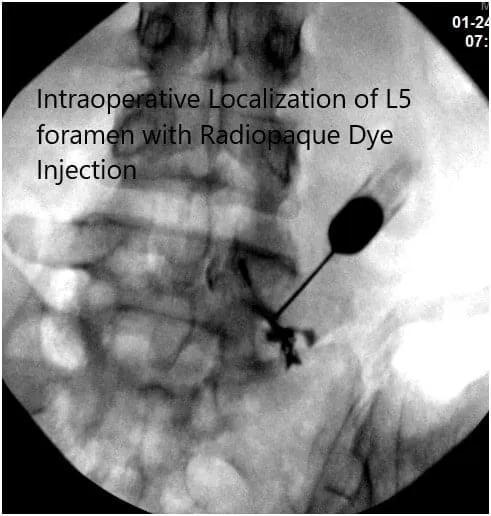

After aseptic prep and drape under C-arm, the needle was introduced to reach the level of the L5-S1 foramen. It was checked under C-arm and found to be in the satisfactory position in AP and lateral view; 0.5 cc of iodine dye was introduced and found to form a good nervogram; 40 mg of Kenalog mixed with 1 cc of 0.5% Marcaine was introduced into the L5 nerve root sheath on the right side.

Intraoperative Fluoroscopy Images.

The patient was on light sedation and was asked about the pain relief. She states there was around 40% pain relief. So, we decided to continue with the injection onto the right S1.